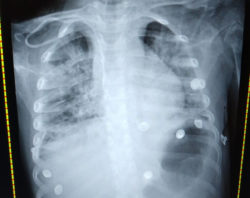

El especialista regiomontano narró días atrás la historia de una niña que permaneció 10 días en terapia intensiva, cuatro de ellos con ventilación mecánica (intubación endotraqueal) por falla en la oxigenación y dificultad para respirar.

Con el permiso de los padres y con el fin de crear conciencia en la comunidad sobre el riesgo para los niños, el médico compartió imágenes de su pequeña paciente, una guerrera como él la llama.

“Esta gran guerrera llegó al hospital Muguerza Alta Especialidad con neumonía muy grave. Después de una semana con cuadro respiratorio gripal en casa con medicamento sintomático”, señala.

Tras los análisis, salió positiva para Covid-19.

Sin duda, agrega, el caso de la pequeña de 5 años marcó historia por ser la primera paciente pediátrica por coronavirus internada de gravedad en el nosocomio.